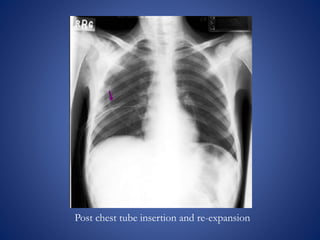

The document discusses chest x-rays and how to analyze them. It describes how densities appear on x-rays, with gas being darkest and bone being lightest. Proper inspiration, penetration, and rotation are needed for quality images. The lungs, heart, bones, and other structures are then analyzed systematically. Common findings like consolidation and air bronchograms are also explained.